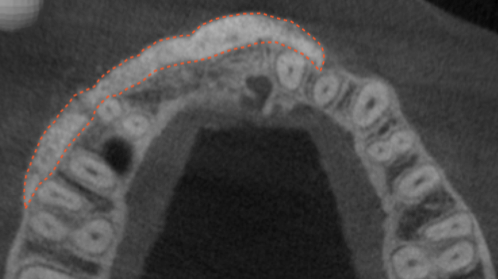

The patient had a congenitally missing upper right lateral incisor. Orthodontic treatment was performed to create the necessary space for a dental implant. Unfortunately, the implant failed, and so did several subsequent attempts to bone graft. These failures resulted in a visible smile deformity, that got worse after each failed procedure.

After the 3rd bone graft failed, the patient sought second opinions. She was a college sophomore at the time. Using a combination of interdisciplinary therapies, including S.M.A.R.T. minimally invasive bone grafting, Dr. Ernesto Lee was able to tridimensionally reconstruct this severe defect and place implants to restore the patient’s smile. The S.M.A.R.T. bone graft was also extended to treat adjacent teeth with thin/dehisced bone.